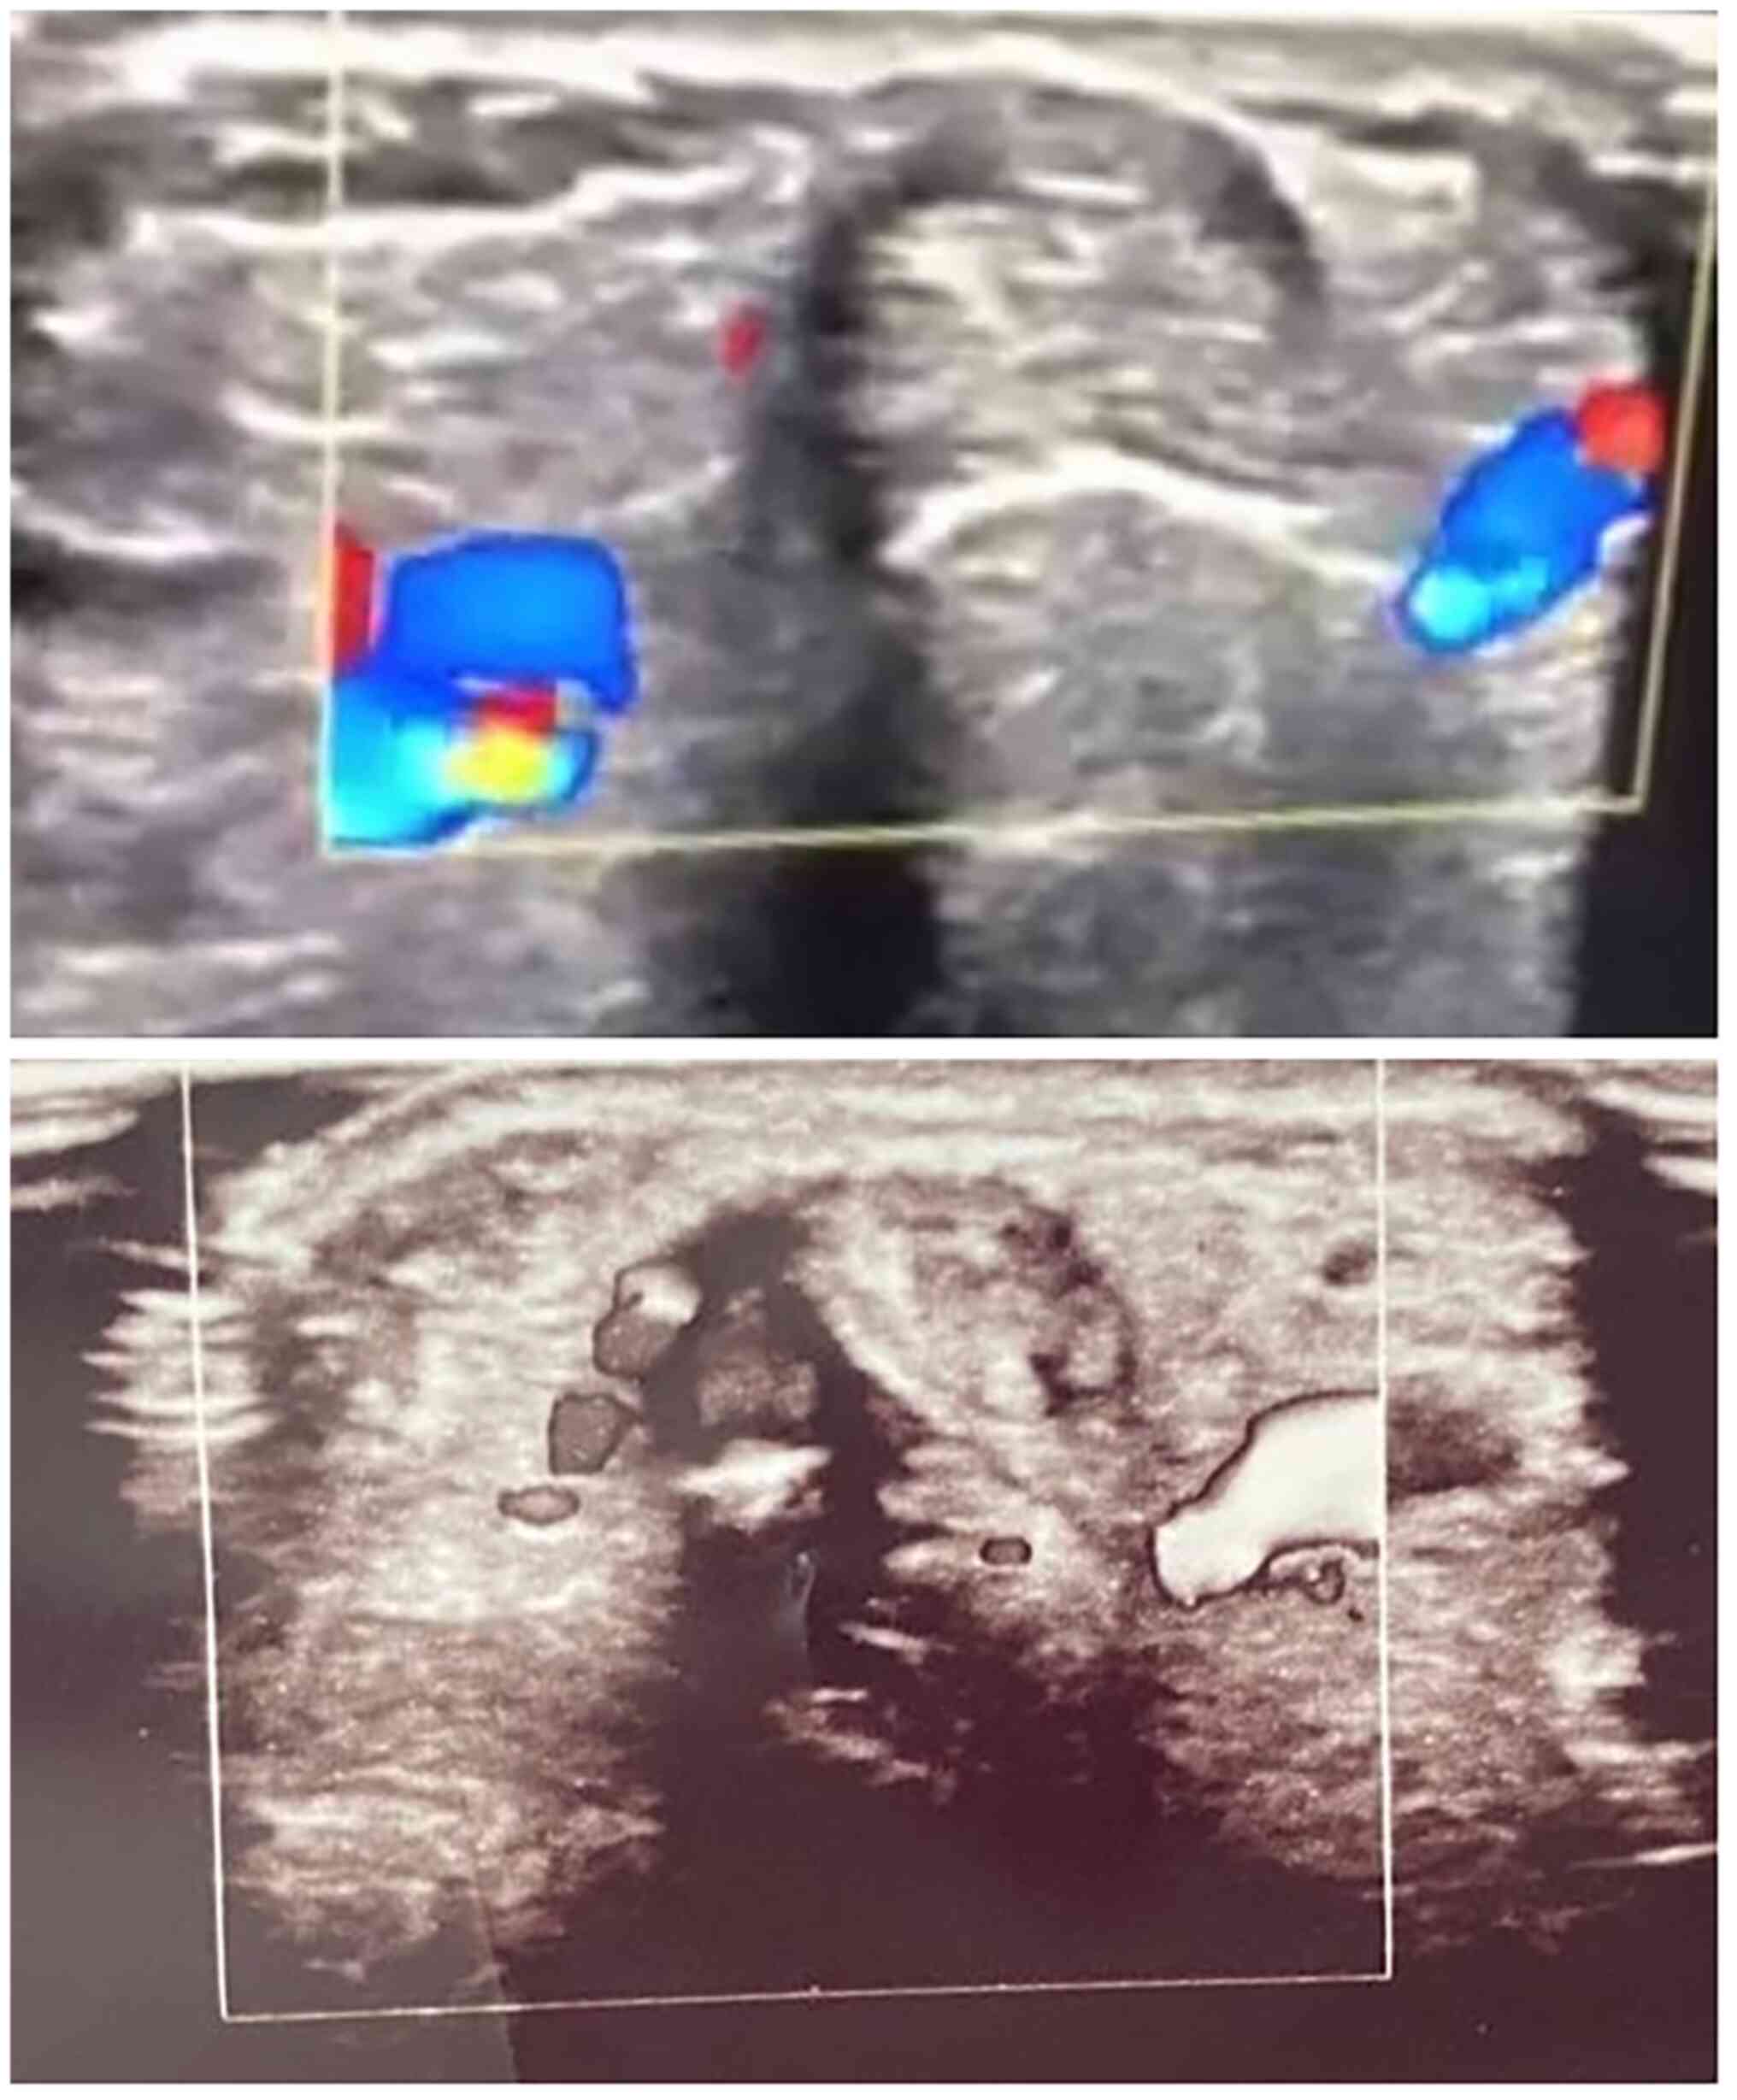

Baseline sonographic findings (as presented in Table III) revealed a thickened retinaculum (1.89±0.5; ranging from 1.3-3 mm) and tendon sheath effusion (2.07±0.52) in all patients (illustrated in Figs. 1 and 2). As regards anatomical variations, 5 patients (41.7%) had septum between APL and EPB, and 4 patients (33.3%) had accessory tendon slips (example illustrated in Fig. 1). However, post-PRP injection, a US examination at the 1- and 3-month follow-up periods revealed a significant improvement in the patients. The thickness of the extensor retinaculum had progressively decreased, from a mean of 1.89 mm pre-injection to a mean of 1.3 mm and 0.96 mm at the 1- and 3-month follow-up, respectively (P<0.001). The tendon sheath effusion observed in all the patients had a mean thickness of 2.07 mm pre-injection. At the 1-month follow-up, effusion was observed in 11 cases (91%) with a mean thickness of 1.6 mm, and at the 3-month follow-up, only 7 of the cases had effusion (58%) with a mean thickness of 0.73 mm (P<0.001). Peri-tendinous hyperemia was initially observed in 7 patients (58.33%), and after the PRP injection this was only observed in 2 patients (16.7%) at the 1-month follow-up (P<0.063) and in no patients (0%) (P<0.001) at the 3-month follow-up (Table III; examples illustrated in Fig. 3). Sonographic improvements observed in two different patients are illustrated in Figs. 4 and 5.

Figure 3

Transverse scan of the first extensor compartment of two different patients (top and bottom panels), illustrating peri-tendinous hyperemia, a thickened retinaculum and tendon sheath effusion.